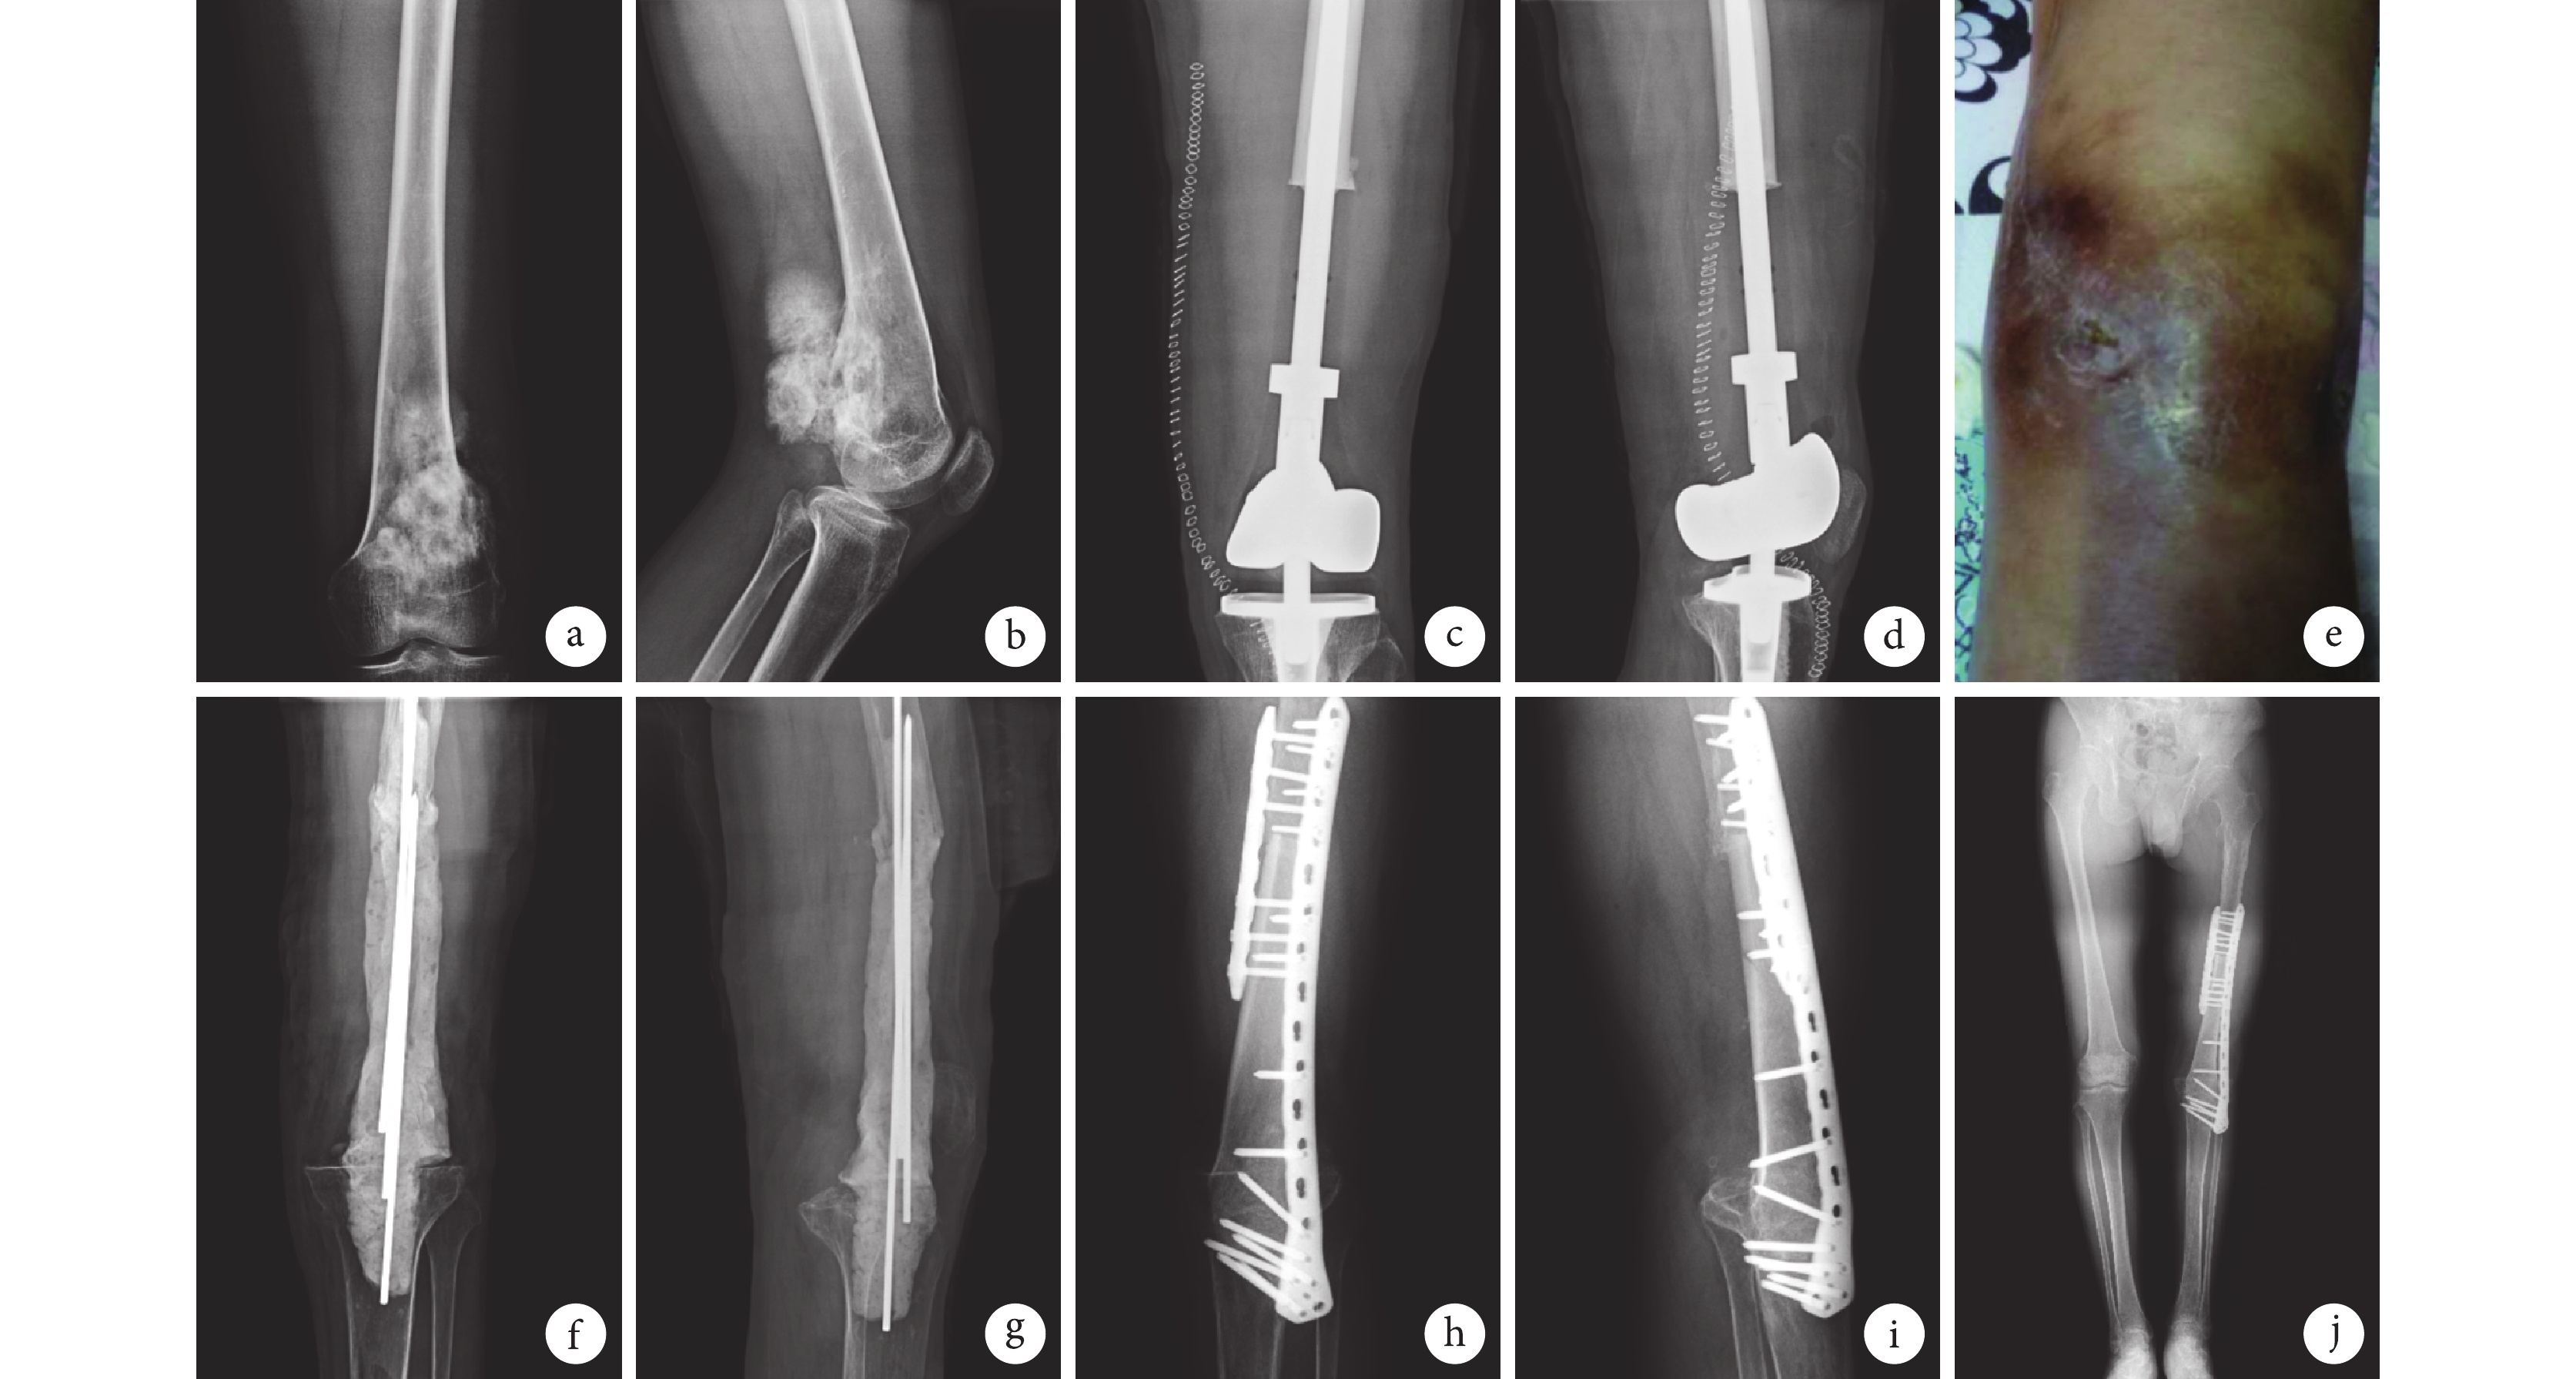

13 例獲隨訪患者術后 12 個月 Enneking 評分為 12~26 分,平均 20 分。其中,2 例急性感染患者分別為 20、23 分,2 例二期截肢患者分別為 12、15 分,2 例帶菌生存者分別為 13、15 分。隨訪期間 1 例發生肺轉移,其余患者均未發現腫瘤轉移征象;腫瘤局部無復發。見圖 1。

a、b. 保肢術前正側位 X 線片;c、d. 保肢術后 1 周正側位 X 線片;e. 保肢術后 22.5 個月發生感染,膝關節皮膚破潰;f、g. 一期術后 3 個月正側位 X 線片;h~j. 二期關節融合術后 12 個月正側位及雙下肢全長 X 線片

Figure1. A 48-year-old male patient with an infection after 22.5 months of limb salvage surgery for distal osteosarcoma of the left femur (case 11)a, b. Anteroposterior and lateral X-ray films before limb salvage surgery; c, d. Anteroposterior and lateral X-ray films at 1 week after limb salvage surgery; e. Infection and skin rupture of the knee joint at 22.5 months after limb salvage surgery; f, g. Anteroposterior and lateral X-ray films at 3 months after the first stage operation; h-j. X-ray films of anteroposterior and lateral views and full length view at 12 months after the secondary arthrodesis